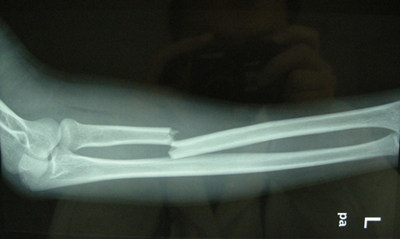

四肢骨折处出现局部迅速肿胀,提示可能是骨折断端刺破血管引起内出血,可临时找些木棒等固定骨折处并可对局部用毛巾等压迫止血;千万不要随意搬动伤肢以免造成骨折端刺破局部血管导致出血。

1、迅速使用夹板固定患处,固定不应过紧;木板和肢体之间垫松软物品,再用带子绑好,木板长出骨折部位上下两个关节,如果没有木板可用树枝、擀面杖、雨伞、报纸卷等物品代替。

2、有破口出血的开放性骨折,可用干净消毒纱布压迫,压迫止不住血时,可用止血带环扎伤口的上方(近心端)止血。

3、大腿骨折时,内出血可达1000毫升(人体总血量大约4000毫升)。包扎固定过紧也能引起神经麻痹,须密切注意患者状况。